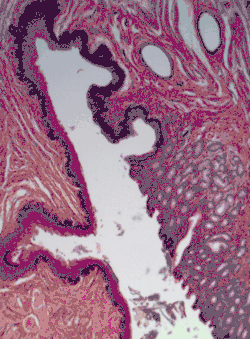

H&E stain of biopsy of normal esophagus showing the stratified squamous cell epithelium.